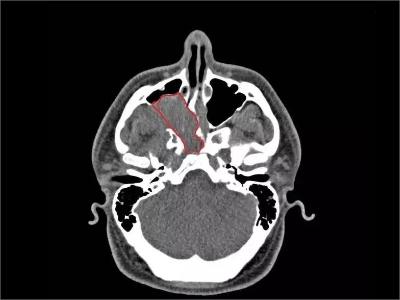

鼻咽纤维血管瘤又名“男性青春期出血性鼻咽血管纤维瘤”,是起源于鼻咽部的良性肿瘤,好发于14-25岁的男性青年,在鼻咽部的良性肿瘤中居首位。侵犯周围组织的能力较强,随瘤体的不断增大,易扩展到眼眶、鼻腔,甚至颅内,导致严重的并发症。

3、其他症状:肿瘤压迫咽鼓管,引起耳鸣、耳闭及听力下降。肿瘤侵入邻近结构则出现相应症状,如侵入眼眶,则出现眼球突出,视力下降;侵入翼腭窝引起面颊部隆起;侵入颅内压迫神经引起头痛及其他颅神经瘫痪。

鼻咽纤维血管瘤发病原因不明,由于患者以青春期男性占明显比例,故认为可能与男性激素的缺乏或女性激

素过剩引起的内分泌功能紊乱有关;肿瘤起源于鼻咽部,枕骨底部或蝶骨体部及翼突内板、上颈椎前部,肿瘤的基底广,可能为该处骨膜增生而形成的。25 岁以后肿瘤逐渐自行消失,是由于蝶枕缝的钙化闭合而影响肿瘤的血供;还可能与感染、创伤有关。